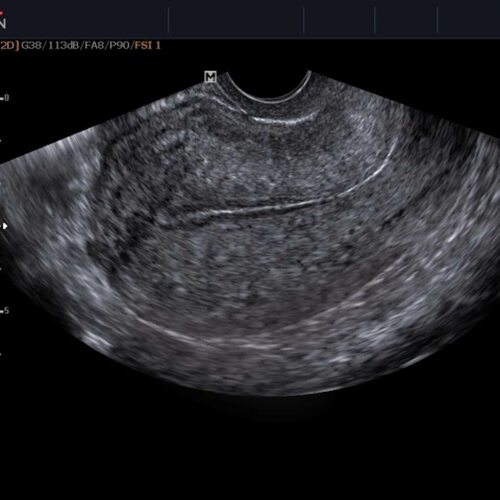

Здоровая матка на УЗИ выглядит как гладкая, однородная структура с ярким контуром. Она имеет определенную форму и размер, которые могут меняться в зависимости от фазы менструального цикла и возраста женщины.

В заключение, здоровая матка на УЗИ выглядит как гладкая и однородная структура с определенной формой и размером. Однако, при возникновении изменений или непривычных симптомов, важно обратиться к врачу для получения профессиональной консультации и дальнейшего обследования.